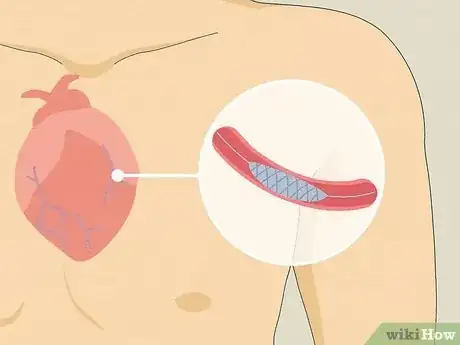

- Left arm pain can have serious causes, like a heart attack or stroke.

If you’re not sure if pain in your left arm is heart-related, pay attention to whether you are also feeling pain in your jaw or heaviness in your shoulders, which may be signs of a heart-related problem. You may also be experiencing nausea, dizziness, cold sweats, or shortness of breath, all of which may be signs of a heart attack. If you believe you may be experiencing a heart attack, call for emergency medical assistance immediately. If the pain in your arm only lasts for a few seconds, or if it lasts for several days, it is unlikely to be caused by a heart problem. To learn more about what the cause of your pain might be, keep reading the article!